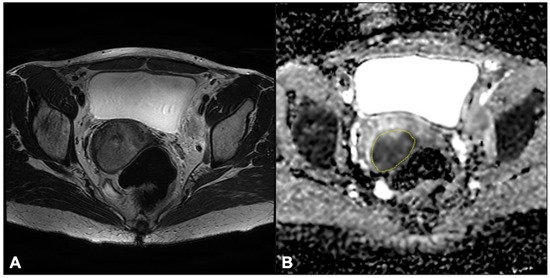

2.3. Image Analysis

2.3.1. DWI-IVIM

2.3.2. ADC